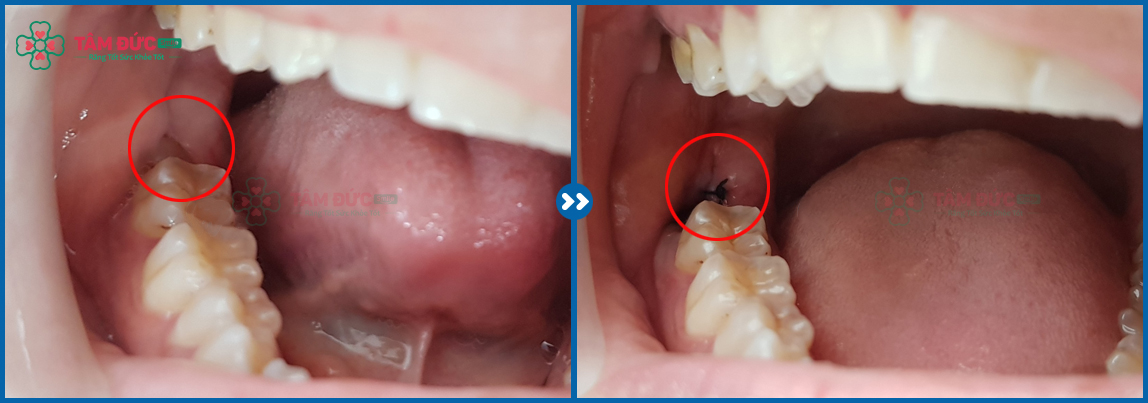

✔ Răng khôn mọc lệch.

✔ Răng khôn mọc ngầm.

✔ Răng khôn mọc kẹt, dính khớp.

Hầu hết những trường hợp mọc răng khôn đều gặp phải tình trạng bất thường: mọc lệch, mọc ngầm hoặc dính khớp, mọc kẹt... nên thực hiện tiểu phẫu nhổ răng khôn đối với những trường hợp này.